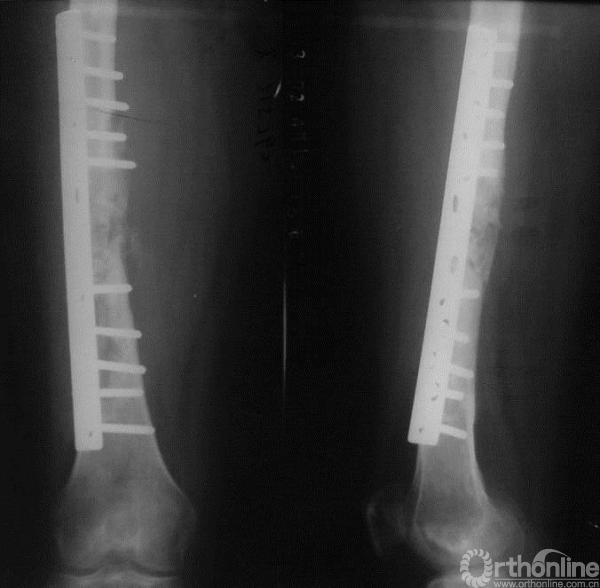

图15-7 第二次术后5个月X线平片正侧位,显示内固定位置良好、植骨未见明显吸收

图15-8 第二次术后10个月X线平片正侧位,显示内固定位置良好、植骨有少量吸收

图15-9 第二次术后21个月X线平片正侧位,可见明显植骨吸收和骨质破坏

2. 患者最初骨折一个月以后出现了明显的外骨痂,病变在髓腔的范围比较局限的,看起来边缘较清楚,考虑良性病变的可能性大,且术前穿刺及术后病理均为良性。第一次术后4个月出现髓内针断裂,考虑固定方式及刮除骨水泥填充影响了骨愈合过程,骨折未愈合才会出现内固定失败,术后病理亦进一步证实未见复发表现。

3. 第二次术后21个月时出现骨质吸收,植骨不愈合,这时应考虑肿瘤复发、感染的可能,否则良性肿瘤骨折植骨此时应已经愈合。

4. 另外一种可能就是肿瘤为恶性,复发后对骨质有破坏。肿瘤为恶性可能是最初时即为恶性肿瘤,发展缓慢,也可能是最初为良性肿瘤,发生了恶变[1]。